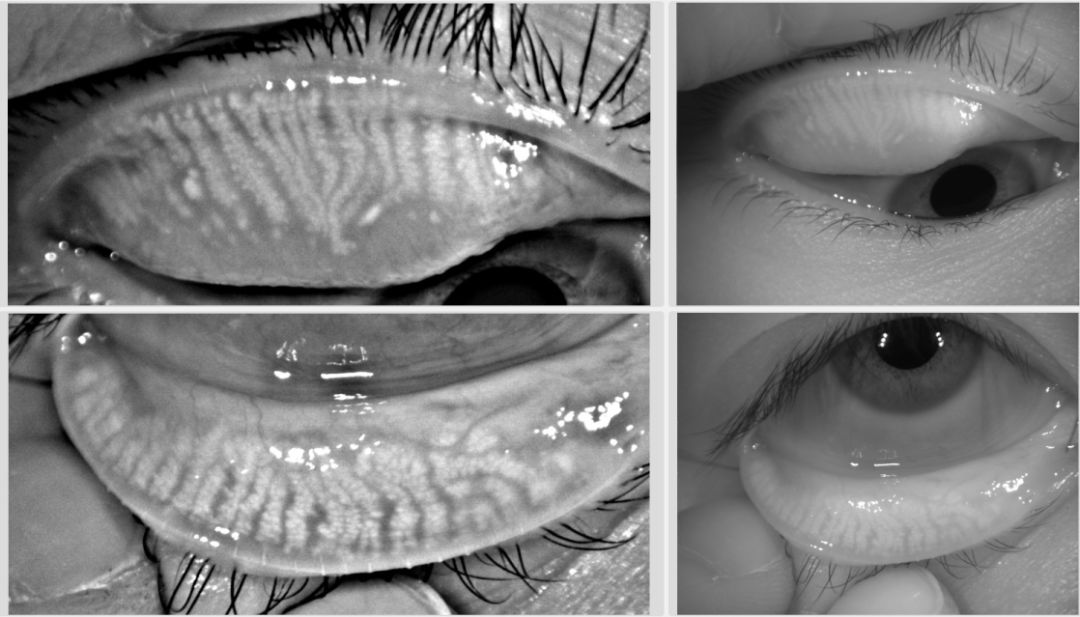

(圖二)中度睑闆腺缺失